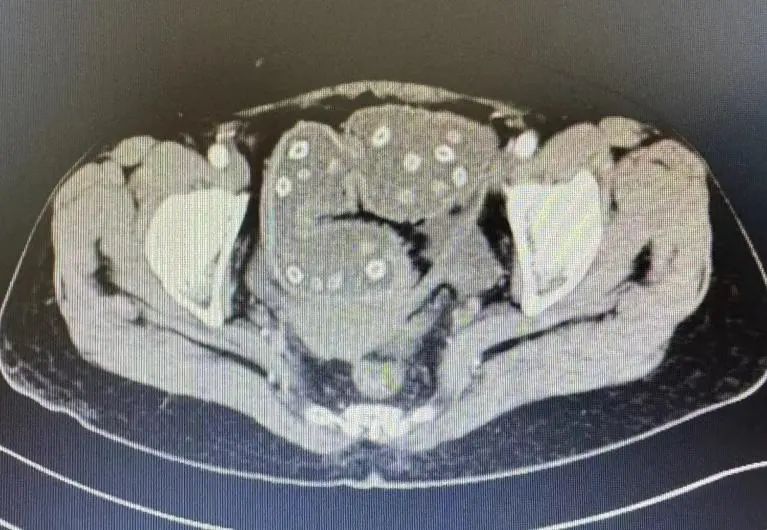

△CT顯示密密麻麻“亮晶晶”的小點點是楊梅核

這一檢查就發(fā)現(xiàn)了大問題——直腸癌!張大媽的腸鏡檢查結(jié)果顯示為“直腸癌伴梗阻”!原來張大媽的直腸因腫瘤變得狹窄,就像塊石頭擋在路中間,吞下去的楊梅核又正好卡在狹窄處,直接給堵住了,導致張大媽無法通氣排便。

正常情況下,人的腸壁是有彈性的,可以收縮,楊梅核也不大,所以可以順利排出;如果腸道長了腫瘤,腸腔會變得狹窄,腸壁也會變得僵硬,楊梅核就容易卡住,導致腸梗阻的發(fā)生。